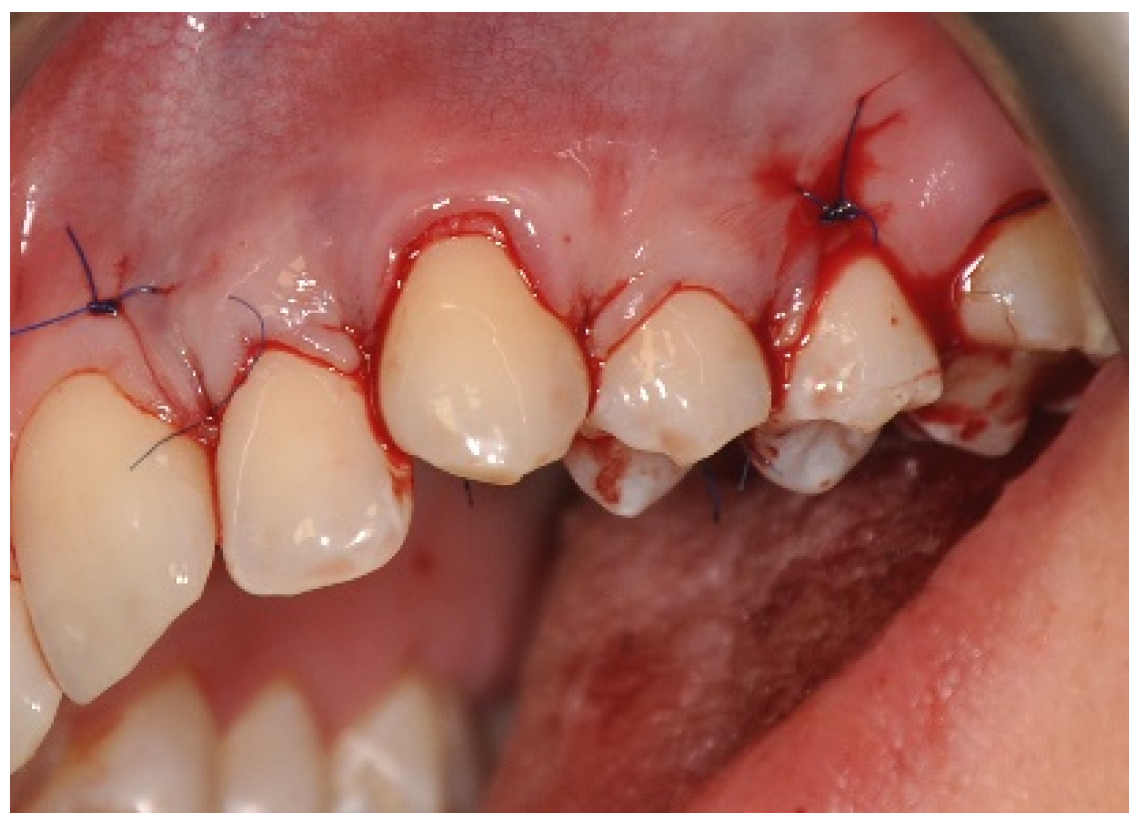

2.3. Surgical Procedures

3.1. Clinical Measurements for CAL and GRD

3.2. Clinical Measurements for GRW, PD and AG